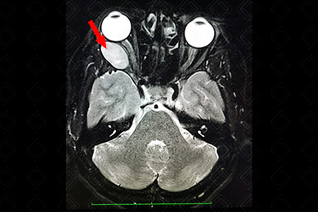

Texto alternativo para a imagem Figura 3. Créditos: Dra. Elazir Mota - Rio de Janeiro/RJ

Descrição da figura 3: Sequência T1 pós-administração do meio de contraste, com ávida captação (seta vermelha).

• Ressonância magnética do crânio: S ão heterogeneamente hiperintensos em T2. Nas imagens ponderadas em T1, são iso ou hipointensos, com ávido realce pelo meio de contraste. A clássica imagem do schwannoma é no ângulo pontocerebelar, pelo acometimento mais comum do VIII par (figuras 1, 2 e 3).